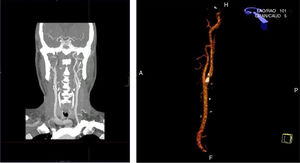

Varón de 73 años con los siguientes antecedentes personales: Carcinoma epidermoide facial derecho y nasal, intervenido, dislipemia en tratamiento con buen control de acuerdo a su riesgo vascular basal. Sin otros factores de riesgo vasculares, en tratamiento con simvastatina 20mg/1comp/24h. No refiere antecedentes de cardiopatía isquémica, ni evento cerebral, ni estados de hipercoagulabilidad. Acude a nuestra consulta para una visita no programada comentando el informe de la tomografía axial computarizada (TAC) con contraste de cuello para estudio de extensión de carcinoma epidermoide facial pedida por el servicio de otorrinolaringología (ORL), objetivando: «Trombosis mural en bulbo carotídeo con extensión a carótida interna derecha y estenosis del 65% de luz», al paciente se le trata con antiagregantes plaquetarios y se pauta estatinas de alta potencia en la consulta de ORL y es enviado a cirugía vascular (CV) de forma preferente.

En la exploración física el paciente se encuentra consciente, orientado en tiempo y espacio. Presión arterial: 130/80mmHg, FC: 90lpm. Auscultación cardiopulmonar: RsCsRs, murmullo vesicular conservado. No se ausculta soplos en región abdominal. Neurológico: no focalidad neurológica. Se realiza ecografía en nuestro centro de salud (CS) objetivando placa en carótida interna derecha: hipoecogénica, heterogénea y calcificada (sombra posterior) que ecográficamente parece un trombo (fig. 1). Nos comunicamos con CV del hospital de referencia y comentamos los diferentes hallazgos, a continuación es remitido para realización de ecografía de troncos supraaórticos reglada donde se objetiva el mismo hallazgo que la ecografía realizada en nuestro CS, la angio-TAC informa como placa de ateroma en carótida interna derecha que provoca una estenosis del 70% (fig. 2). Se realiza TAC cerebral y aortoilíaco, sin alteraciones. Al paciente se le mantiene en tratamiento con estatinas de alta potencia y con antiagregantes plaquetarios.